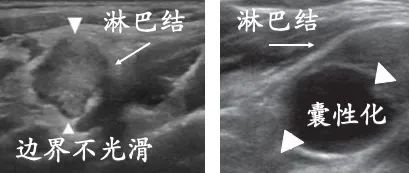

3 一定面积的转移

再多一些的癌细胞入驻淋巴结后

它的结构将发现显著的变化

这种变化很容易被超声捕捉

一定面积转移的淋巴结已经丢失了正常的结构

短边超过8毫米

左图淋巴结内部回声非常不均匀

边界也不光滑,提示结外侵犯

右图淋巴结中能发现明显的囊性成分

做病理能发现

转移灶大于8毫米,甚至还有结外侵犯

当淋巴结转移进展到这种程度

通常是建议手术的